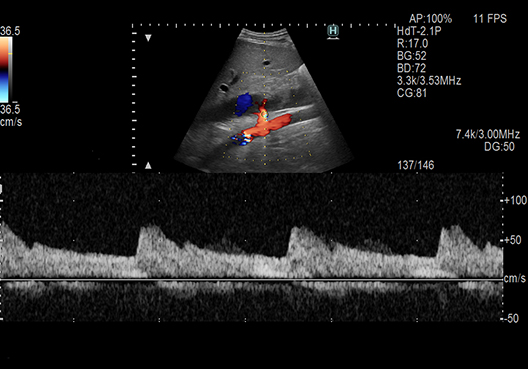

Settings like the position of Color ROI and cursor can be set by a single click operation in Doppler examination of a vessel. Convex transducers are supported as well. Additionally, it is possible to measure the intima media thickness (IMT) automatically by AutoIMT.

eTRACKING*1

Wave Intensity (WI)*1

Unique functions to support more detailed evaluation of hemodynamics are supported.